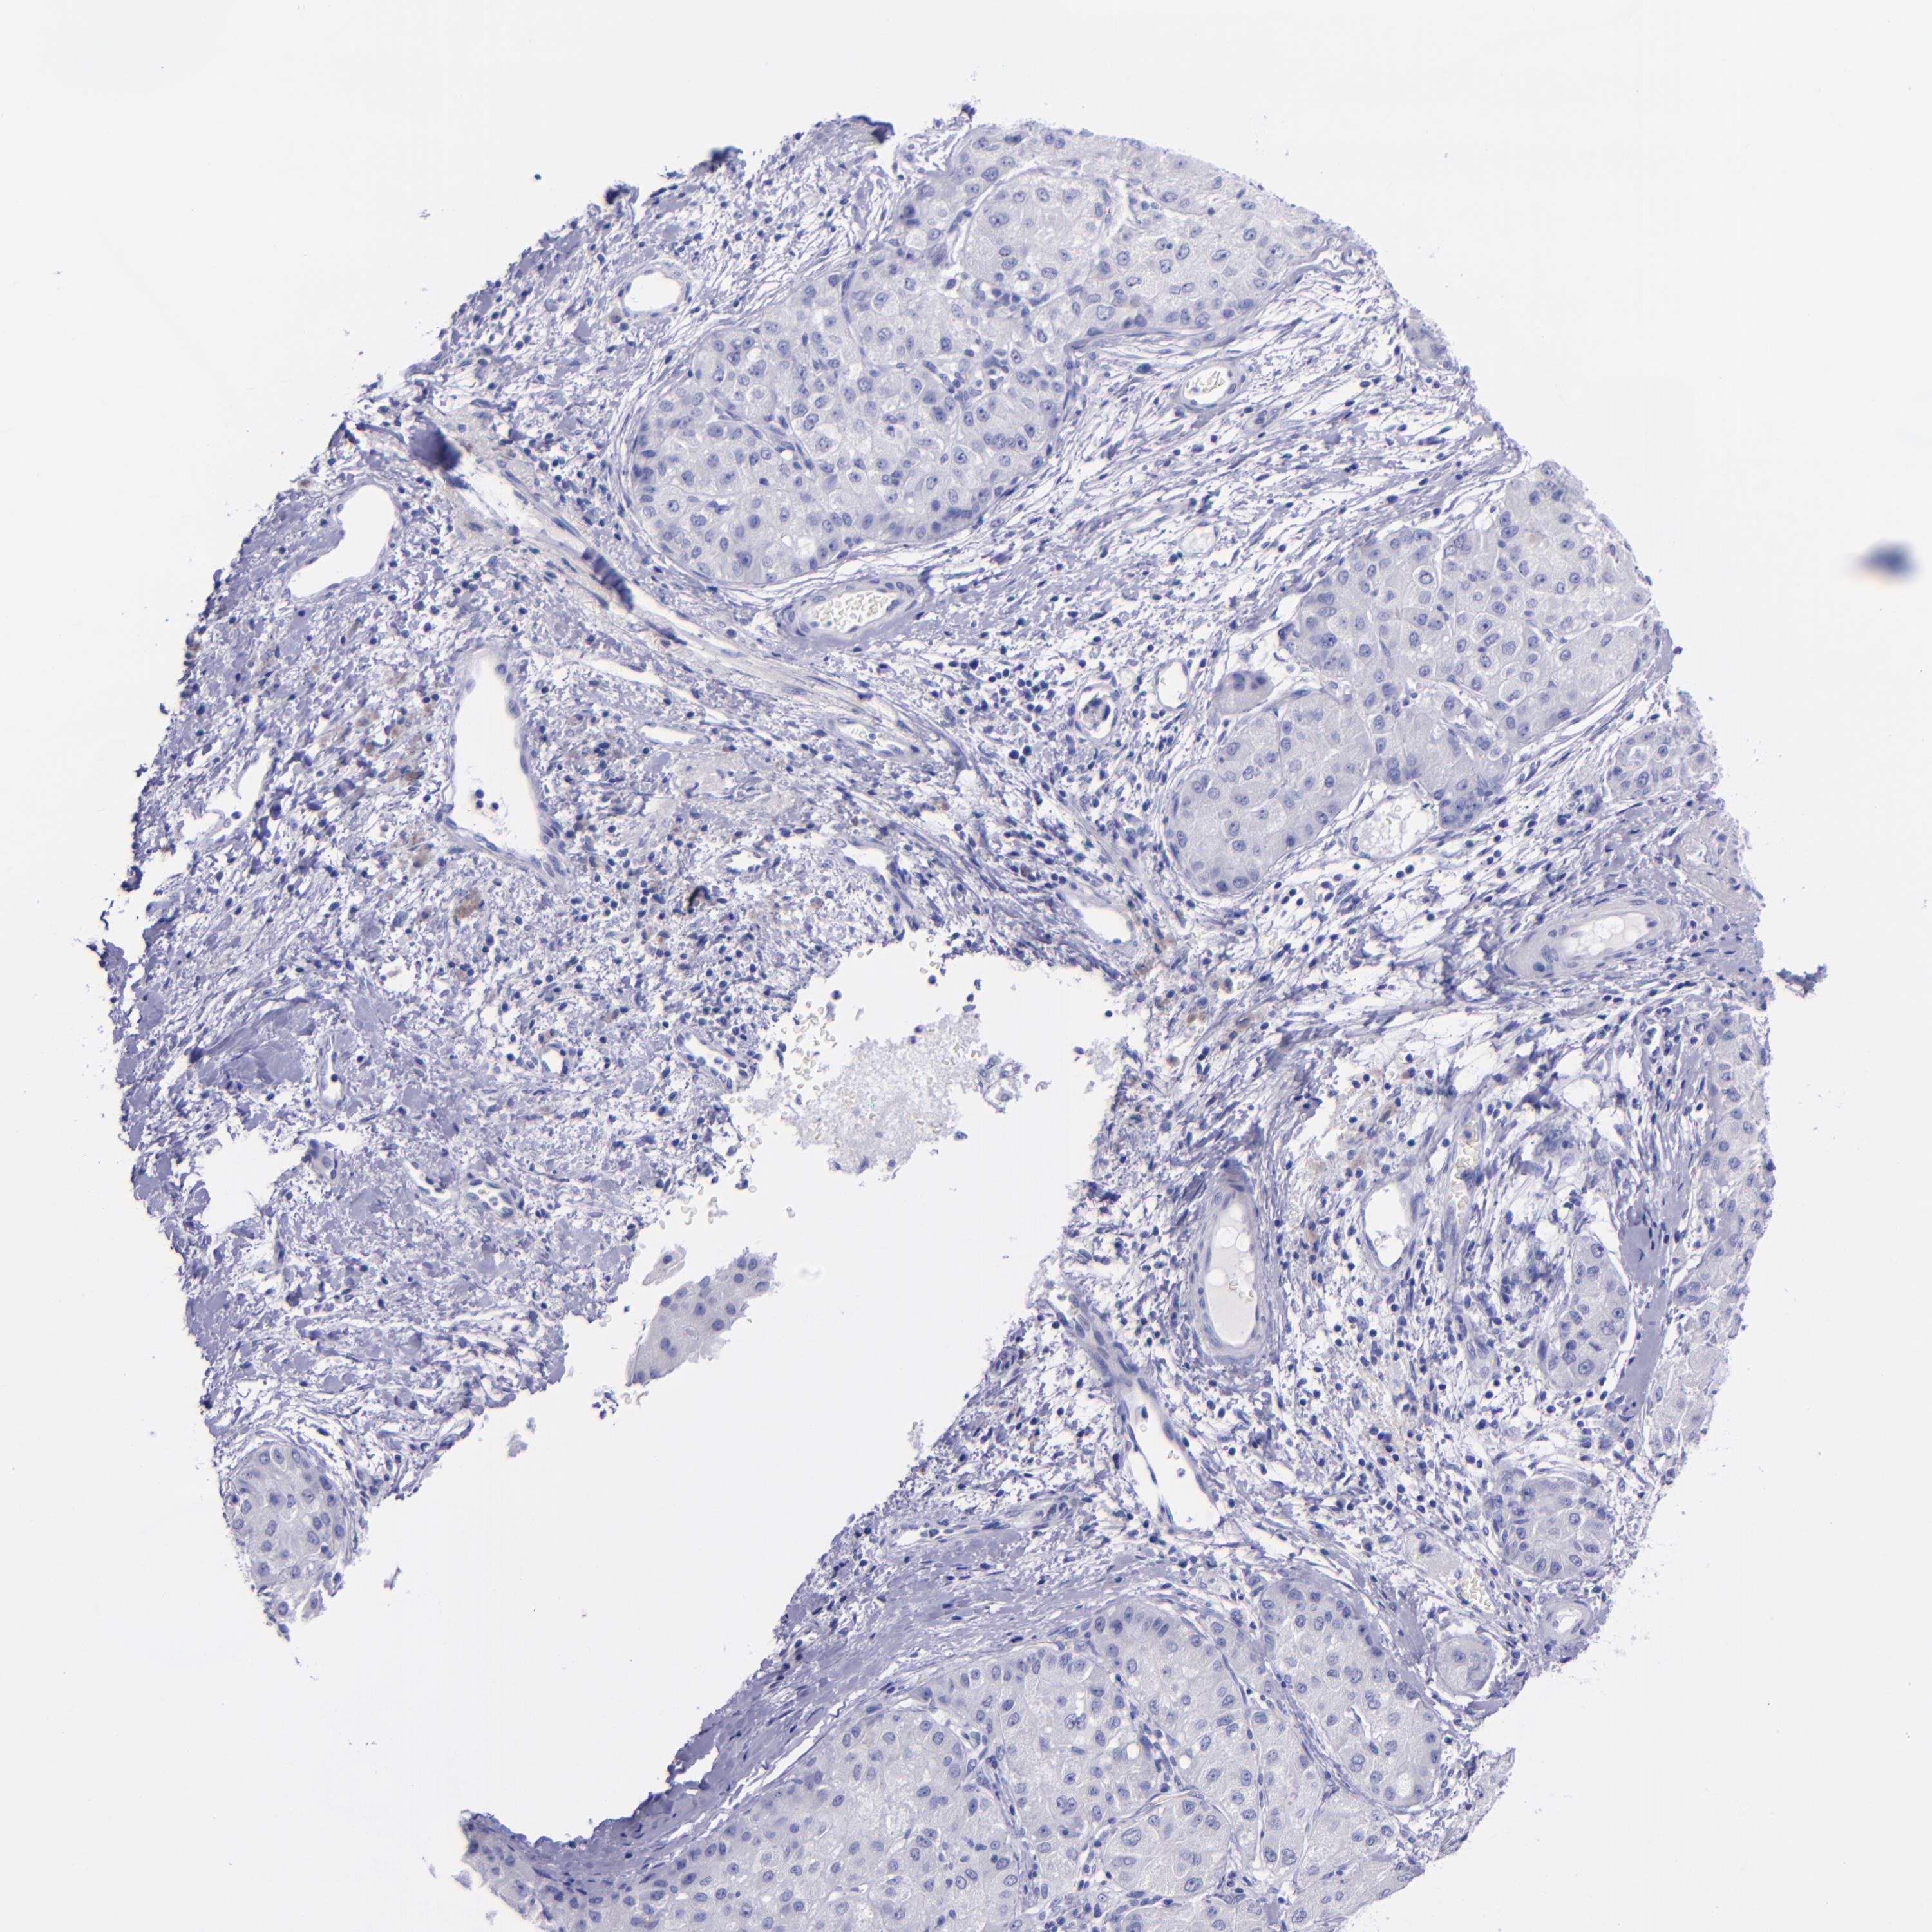

LIVER CANCER - Protein expressioni

A mouse-over function shows sample information and annotation data. Click on an image to view it in a full screen mode. Samples can be filtered based on level of antibody staining by selecting one or several of the following categories: high, medium, low and not detected. The assay and annotation is described here.

Note that samples used for immunohistochemistry by the Human Protein Atlas do not correspond to samples in the TCGA dataset.

Antibody stainingi

Antibody staining in the annotated cell types in the current human tissue is reported as not detected, low, medium, or high, based on conventional immunohistochemistry profiling in selected tissues. This score is based on the combination of the staining intensity and fraction of stained cells.

Each image is clickable and will lead to virtual microscopy that enables deeper exploration of all samples and also displays staining intensity scores, fraction scores and subcellular localization as well as patient and tissue information for each sample.

Antibody HPA007863

Antibody CAB002226

Staining

High

Medium

Low

Not detected

Intensity

Strong

Moderate

Weak

Negative

Quantity

>75%

75%-25%

<25%

None

Location

Nuclear

Cytoplasmic/membranous

Cytoplasmic/membranous,nuclear

Cholangiocarcinoma

Carcinoma, Hepatocellular, NOS